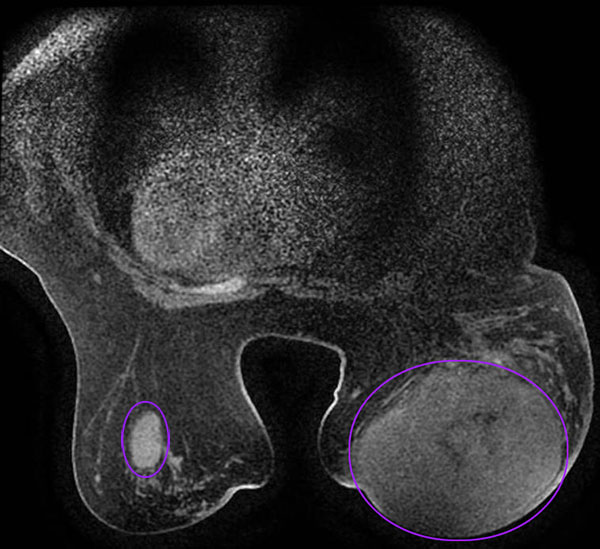

乳腺MRI增强显示右乳巨大肿物和左乳肿物

Syria 今年40岁,来自叙利亚,因右侧乳腺巨大肿瘤(直径达15厘米)辗转多家医院,历时七年。2024年在当地医院做了穿刺,后经友人介绍来到中国广州求医,先在某医院就诊,被告知她的病情需多次手术才能解决。经多方打听,最终选择我院求助。

就诊时,肿瘤已严重压迫胸壁,影响其日常活动及肩部功能,同时因双侧乳房形态差异显著,患者长期承受着心理压力。乳腺肿瘤科主任王坤院长组织团队全面评估后,制定了“肿瘤扩大切除+双侧乳房对称性重塑”的个性化手术方案,在彻底切除肿瘤的同时,兼顾术后形态的自然与对称。